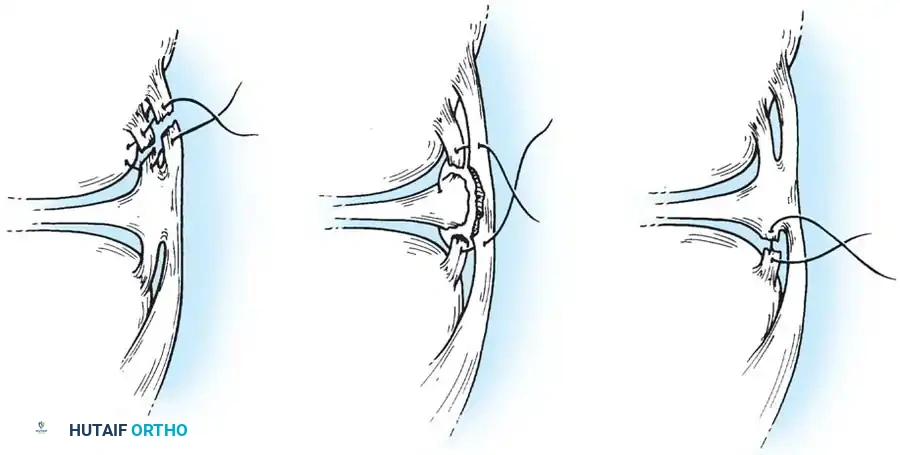

Medial Collateral and Capsular Repair

For acute medial-sided repairs, a longitudinal incision is made over the medial aspect of the knee, extending from the medial epicondyle to the anteromedial tibia.

Image

The deep fascia is incised, and the sartorius fascia is identified. The superficial MCL is exposed. If the injury is an avulsion from the femoral origin or tibial insertion, it is repaired using heavy non-absorbable sutures and suture anchors.

Mid-substance tears are meticulously re-approximated. The deep capsular ligaments (meniscofemoral and meniscotibial) must be inspected. If the medial meniscus is peripherally detached, it is repaired to the capsule prior to tensioning the superficial MCL.

In cases of severe tissue maceration or chronic attenuation, the ligament may need to be advanced and secured to the bone using a spiked ligament washer or a cortical button to restore appropriate valgus stability.